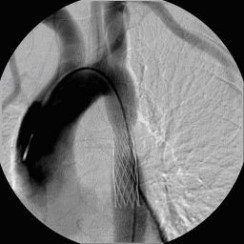

Erfolgreiche Implantation eines transjugulären intrahepatischen portosystemischen Shunts (TIPSS) bei Leberzirrhose und refraktärem Aszites. Implantation eines Stentgrafts

(Bild 4 von 4)